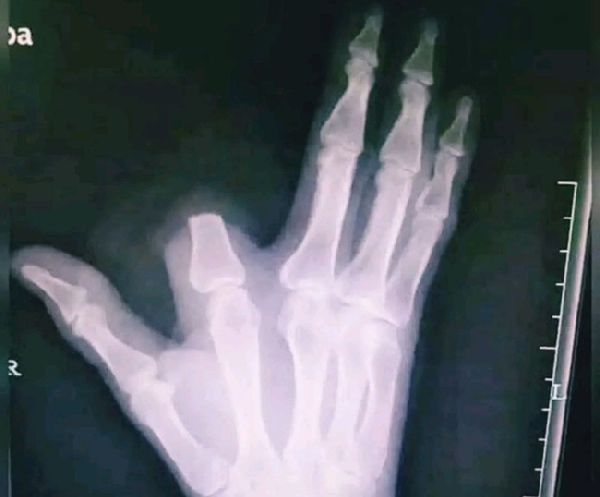

Mordu, il panique et commet le pire avant de savoir que le serpent n'était pas venimeux

Morsure de serpent